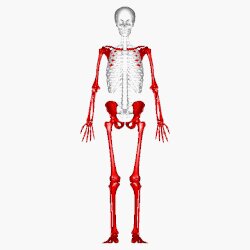

بخش ها:

اسکلت مرکزی یا محوری: جمجمه، ستون مهره، دندهها، استخوانهای سینه

اسکلت ضمیمهای: استخوانهای دست و پا، شانه و لگن خاصره

۱. تعداد استخوانهای بدن انسان ۲۰۶ قطعه است که به وسیله مفاصل به هم ارتباط دارند.